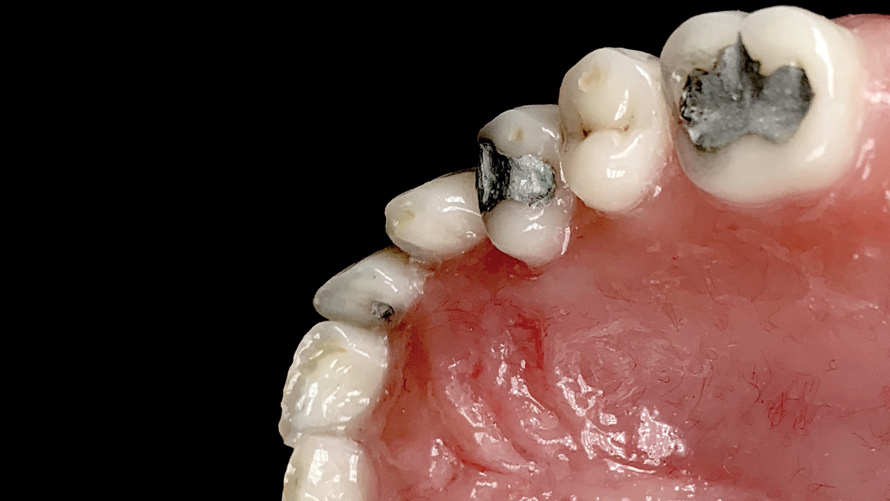

(18.) Tooth shade analysis of value, chroma, and hue taken with a smartphone and an EALS device.

Figure 18

(19.) Tooth shade analysis of value, chroma, and hue taken with a smartphone and an EALS device.

Figure 19

Shade Selection and Laboratory Communication

The most utilized intraoral photographs in the field of dentistry are perhaps those that capture shade information (Figure 18 and Figure 19). The analysis of color (ie, value, chroma, hue) in dentistry is a critical step in the fabrication of esthetic indirect restorations, such as all-ceramic crowns and porcelain laminate veneers. The ability to properly communicate this information with the dental laboratory is essential to ensure an appropriate shade match, a reduction in chairtime and overhead, and most importantly, a satisfactory patient experience and treatment outcome. In recent years, the use of polarized light photography as an aid in the shade selection process has become extremely popular. For some EALS devices, special polarizing filters have been specifically designed to fit over the light-emitting portion of the device (Figure 20 and Figure 21). The images produced using polarized light photography demonstrate an elimination or reduction in the specular reflection of hard and soft tissue, resulting in a matte-finish appearance of the dentition and gingiva. These types of photographs aid the ceramist in identifying areas of opacity and translucency, crack lines, hypo- or hypercalcification, and other internal features of the dentition that may not be readily visible without such a filter (Figure 22).